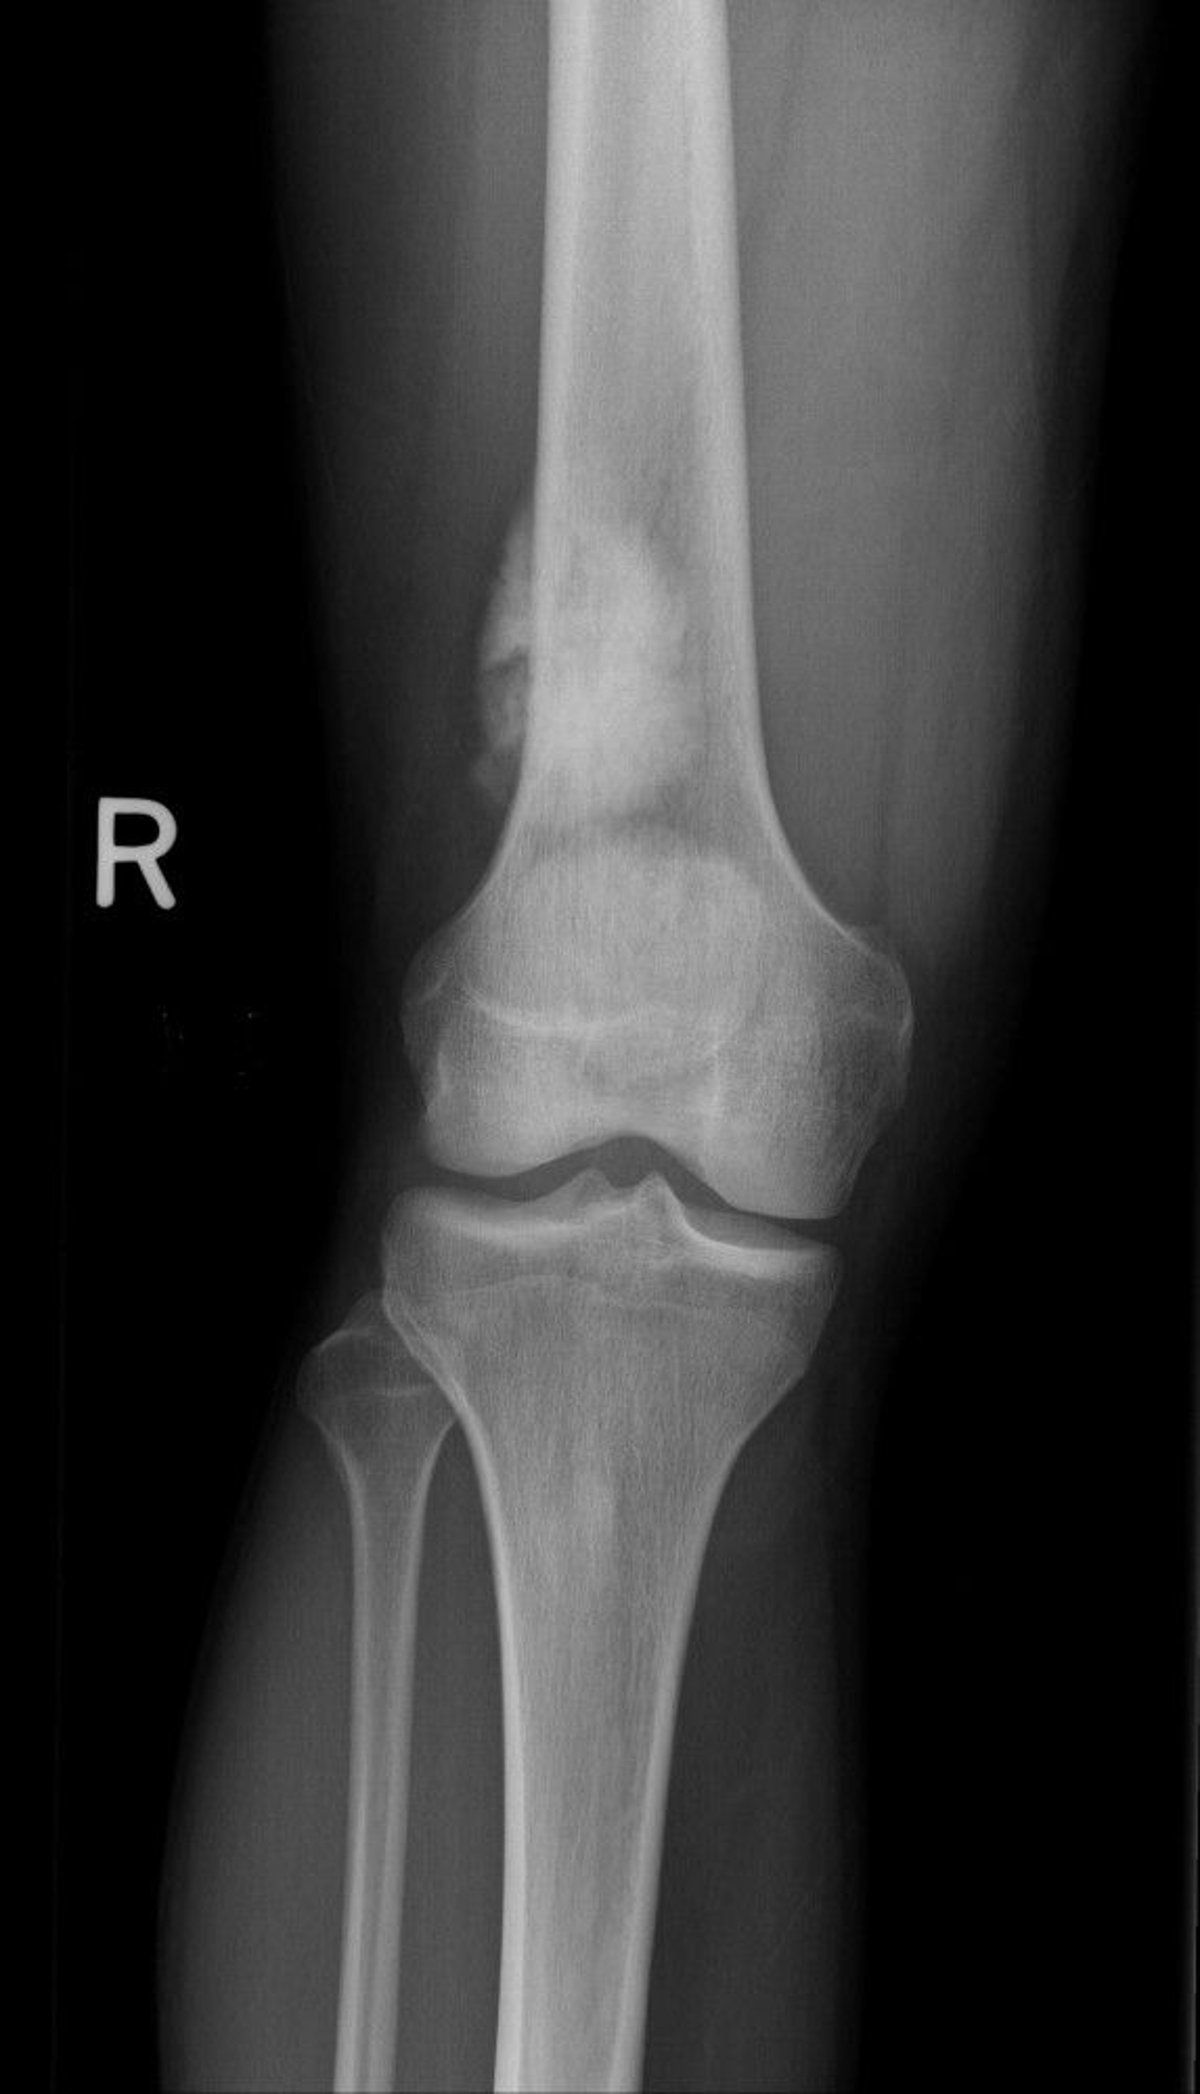

Osteosarkoma adalah jenis tumor tulang kanker primer yang paling umum jika multiple myeloma dianggap sebagai tumor hematologi. Meskipun paling banyak terjadi pada anak-anak dan remaja, osteosarkoma dapat terjadi pada usia berapa pun. Anak-anak yang membawa gen retinoblastoma herediter dan sindrom Li-Fraumeni berisiko lebih tinggi mengalami osteosarkoma. Lansia di atas 60 tahun, terutama yang menderita penyakit Paget pada tulang, orang yang telah menjalani terapi radiasi tulang untuk kanker lain, atau yang memiliki area jaringan tulang mati (disebut infark tulang) dan kondisi lain, terkadang menderita jenis tumor ini.

Osteosarkoma biasanya terjadi di dalam atau di sekitar lutut, tetapi dapat bermula dari tulang mana pun. Tumor ini cenderung menyebar (bermetastasis) ke paru-paru atau tulang lainnya. Biasanya, tumor ini menyebabkan nyeri dan pembengkakan atau akumulasi jaringan lunak, dan hilangnya gerakan sendi.

Pemeriksaan sinar-x dan pengambilan sampel jaringan untuk pemeriksaan dengan mikroskop (biopsi) diperlukan untuk mendiagnosis osteosarkoma. Diperlukan foto sinar-x pada dada dan pemindaian tomografi terkomputasi (CT) pada dada untuk mendeteksi kanker yang telah bermetastasis ke paru-paru, dan pemindaian tulang diperlukan untuk mendeteksi kanker yang telah menyebar ke tulang lain. Pencitraan resonansi magnetik (MRI) dan tomografi emisi positron (PET) yang dikombinasikan dengan tomografi terkomputasi (PET-CT) adalah uji pencitraan lain yang juga dilakukan.

Pemeriksaan sinar-x pada lutut ini menunjukkan osteosarkoma pada tulang paha di atas lutut.

Gambar milik Michael J. Joyce, MD, dan Hakan Ilaslan, MD.